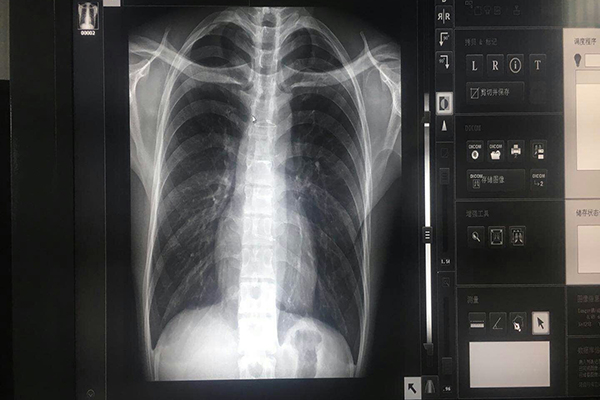

為了使放射學(xué)界對數(shù)字影像系統(tǒng)的診斷準(zhǔn)確性問題有充分的認(rèn)識,了解醫(yī)用顯示器在數(shù)字影像中的作用.顯示器i中灰階是什么?灰階是指顯示器顯示從亮值到黑值之間所能夠顯示的層次。灰階是真實顯示醫(yī)學(xué)圖像中患者病灶的一個重要參數(shù),只有灰階的層次多,才能夠保證較高的讀片質(zhì)量。普通顯示器有8bit-?256灰階,用于顯示彩色的圖象,無灰階要求;醫(yī)用顯示器有10?bit-1024灰階,用于顯示X光灰階圖象,于診斷相關(guān)。

分辨率是指單位面積顯示像素的數(shù)量,同時顯示器的成本與分辨率也成成正比。選擇普通顯示器分辨率為1024×768,用于辦公文字是可以滿足的。但是在低分辨下通過對軟件處理來顯示高分辨率影像時,需要對顯示畫面的內(nèi)容做出改動,比如改變部分醫(yī)學(xué)像素的內(nèi)容,再通過對該像素周圍的像素進(jìn)行對比后,“生成”新的像素,插入到顯示畫面中。

響應(yīng)時間指的是液晶顯示器對輸入信號的反應(yīng)速度,也就是液晶由轉(zhuǎn)亮或由亮轉(zhuǎn)暗的反應(yīng)時間。通常都是以毫秒(ms)來計算。響應(yīng)時一般說來分為兩個部分—上升時間和下降時間,而我們所說的響應(yīng)時間指的就是兩者之和。醫(yī)用顯示器的尺寸與分辨率有連帶關(guān)系。分辨率愈高,尺寸愈大,但并不成正比關(guān)系.生產(chǎn)廠在制造時已考慮到和膠片接近一致性的尺寸了。普通顯示器則沒有這方面的考慮。醫(yī)用顯示器的穩(wěn)定性、整體性和一致性:如果隔了一段時間,同一圖像其顯示質(zhì)量還是一樣,利昂灰階顯示器怎么樣?猶如看同一張膠片一樣。整體性是指在醫(yī)院內(nèi)不同地點的工作站上顯示的同一圖像其亮度、灰度、對比度等是完全一樣的。